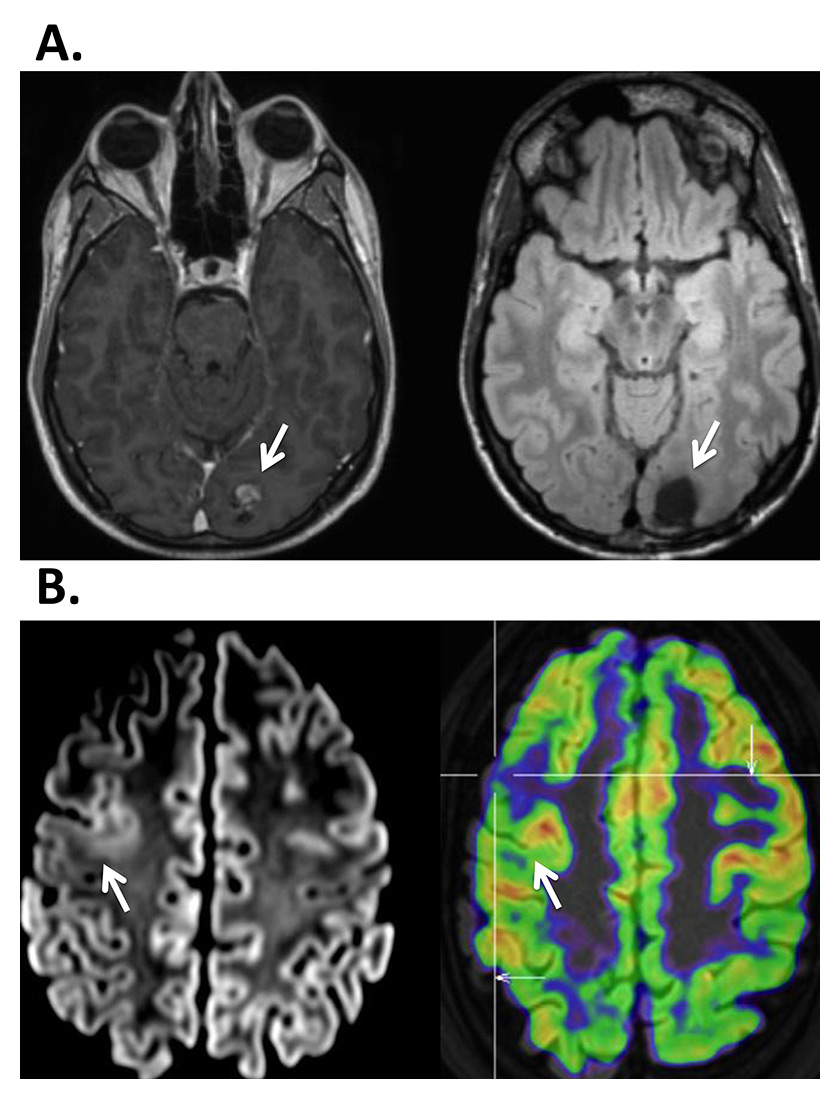

Surgical results depend critically on the definition of the ictal and interictal EEG onset zone as well as on the presence of a lesion in 1.5-Tesla or, better, 3-Tesla high-resolution MRI, obtained with an epilepsy protocol, i.e. 1 mm slices for most sequences, as detailed elsewhere [98]. If the lesion is highly suspected or functionally localised with PET, SPECT or ESI, but not visualised in the high-resolution MRI, additional statistical analysis of the MRI may be useful and unravel the underlying epileptogenic lesion [99, 100] (fig. 3).

Figure 3

A. 37-year-old patient presenting with seizures with a visual aura in the right visual field. On MRI a left occipital cavernoma was found (à), which was surgically removed (right). Work-up did not show any other focus or area of dysfunction. B. 34-year-old patient presenting with generalized seizures, EEG showed a very active focus in the right frontal lobe, but MRI was considered normal. Right: PET identified a focal hypometabolism in the right frontal lateral area (à). Left: Review of the MRI showed blurring between gray and white matter indicating the presence of a dysplasia.

EEG = electroencephalogram; MRI = magnetic resonance imaging; PET = positron emission tomography